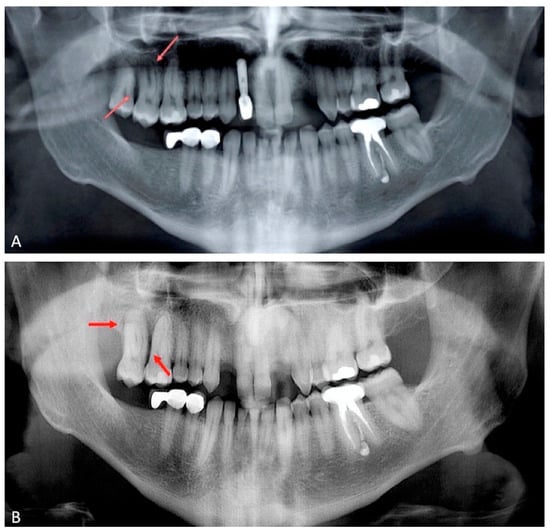

2.1. Case Presentation